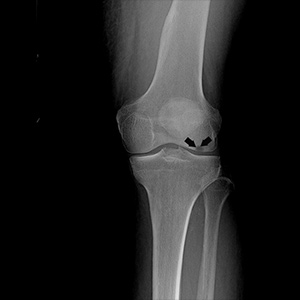

Picture of Osteochondritis Dissecans

Osteochondritis Dissecans

Osteochondritis dissecans is a joint condition in which a piece of cartilage, along with a thin layer of the bone separates from the end of the bone because of inadequate blood supply. The separated fragments are sometimes called “joint mice”. These fragments may be localised, or may detach and fall into the joint space causing pain and joint instability.